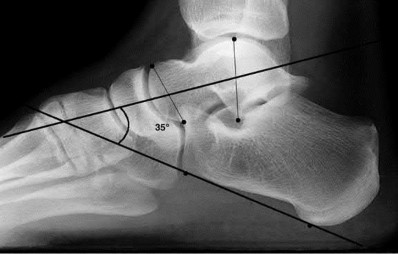

A 25-year-old male sustains an ankle fracture dislocation and undergoes open reduction and internal fixation. He returns to clinic five months following surgery complaining of continued ankle pain and instability with weight bearing. His immediate post-operative AP radiograph is seen in Figure A. Which of the following could have prevented this patient from developing persistent pain?

The patient presents with continued ankle pain and instability following open reduction and internal fixation. The radiograph in figure A demonstrates inadequate restoration of fibular length, likely leading to continued tibiotalar instability.

Illustration A demonstrates fibular malreduction with dislocation of the fibula anterior to the tibial incisura. Illustration B shows a comminuted fibula fracture along with a measurement of length from an intact fibula. The arc from the lateral process of the talus to the peroneal groove of the distal fibula is known as the "dime" sign and should remain unbroken if fibular length has been restored. Illustration C demonstrates the use of a push-pull screw and lamina spreader to regain length intraoperatively for a comminuted fibula fracture.

Chu and Weiner review management of malunions of the distal fibula. The authors state that restoration of fibular length, alignment and rotation leads to reduction of the talus, provides a buttress to talar motion in the setting of an incompetent deltoid, and allows the syndesmotic ligaments to heal at the appropriate tension.